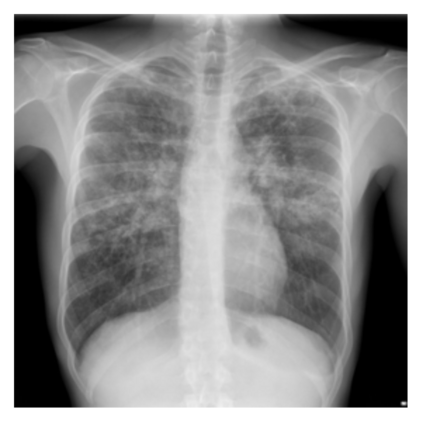

The evaluation of infectious disease processes on radiologic images is an important and challenging task in medical image analysis. Pulmonary infections can often be best imaged and evaluated through computed tomography (CT) scans, which are often not available in low-resource environments and difficult to obtain for critically ill patients. On the other hand, X-ray, a different type of imaging procedure, is inexpensive, often available at the bedside and more widely available, but offers a simpler, two dimensional image. We show that by relying on a model that learns to generate CT images from X-rays synthetically, we can improve the automatic disease classification accuracy and provide clinicians with a different look at the pulmonary disease process. Specifically, we investigate Tuberculosis (TB), a deadly bacterial infectious disease that predominantly affects the lungs, but also other organ systems. We show that relying on synthetically generated CT improves TB identification by 7.50% and distinguishes TB properties up to 12.16% better than the X-ray baseline.